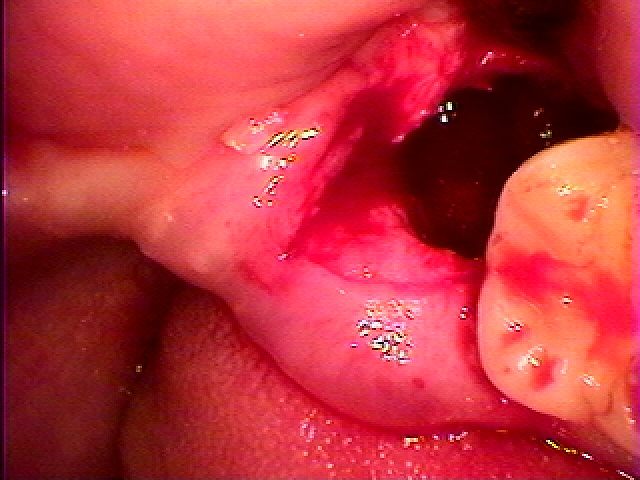

最小限で開けていきました

歯冠部を取り出しました